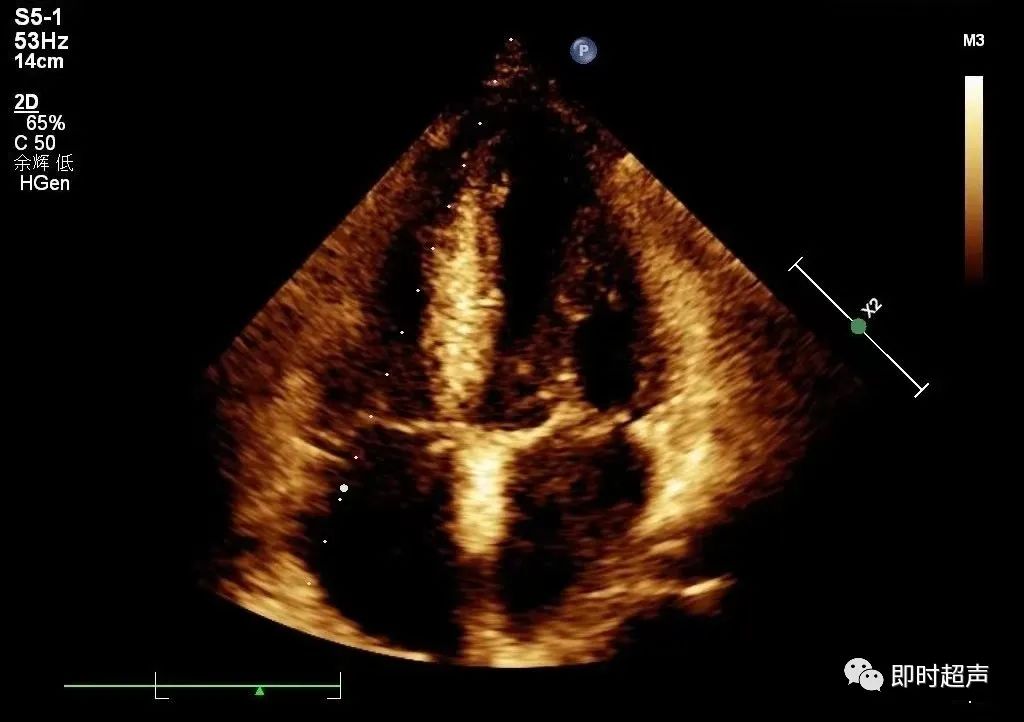

★左心房内径

测量时相:心室收缩末期;左房前后径:胸骨旁左室长轴切面,从主动脉远端后壁取垂直线到左房后壁进行测量;左房长径:心尖四腔心切面,从二尖瓣环平面中点到左心房顶的距离(不一定垂直于二尖瓣环平面)。

房横径:

心尖四腔心切面,从房间隔中点到左心房侧壁,并且垂直于左房长径;左房面积:心尖四腔心描记,应避开左心耳及肺静脉汇合处;左房容积:在心尖四腔心及两腔心切面,用双平面Simpson测量。